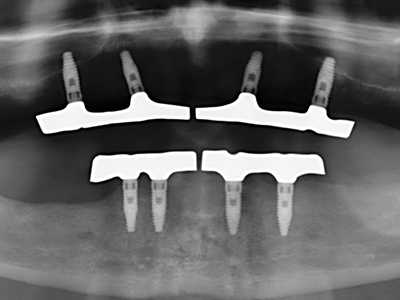

Индикация: Костно разделяне/ шиниране?

Костната тъкан е не само минерализирана структура, тя съдържа и съществено количество колагенови влакна. Това означава, че тя има не само добра компресивна сила, но и известна степен на гъвкавост, която може да се възприеме като предимство при извършване на костна аугментация. В класическата процедура по разширяване чрез костно разделяне, атрофиралият алвеоларен гребен е разделен надлъжно и внимателно разширен след достигане на подходящата остеотомна дълбочина (Фиг. 13-16), в идеалния случай без допълнително отстраняване на периостеума (Brugnami, Caiazzo et al. 2014, Stricker, Fleiner et al. 2014). Системите с винт и пластини с увеличаване на разстоянието при разширяване са доказали ефективността си при разделяне на двете костни ламели, оставайки под прага на фрактурите. В общи линии, оставащата ширина на костта от поне 3–4 mm е задължителна (Chiapasco, Zaniboni et al. 2006), за да се гарантира добра гъвкавост и достатъчно костно покритие за бъдещото поставяне на импланти. Ако е необходимо, вертикалната остеотомия на едната или двете страни може да подобри гъвкавостта. Комбинацията с допълнителни техники за аугментация, особено в букалната страна, е описана като алтернатива на класическата техника.

Процедурата по разделяне е атравматична и няма голяма загуба на пространство, използвайки пиезотриони, и няма значителна разлика между импланти в разделени челюсти и импланти в алвеоларния гребен без костен дефицит (Chiapasco, Zaniboni et al. 2006, Danza, Guidi et al. 2009). Въпреки това, важно е да има достатъчно и продължително охлаждане, особено при ограничено и дълбоко разделяне, за да се избегне термичен стрес в апикално-остеотомните зони.